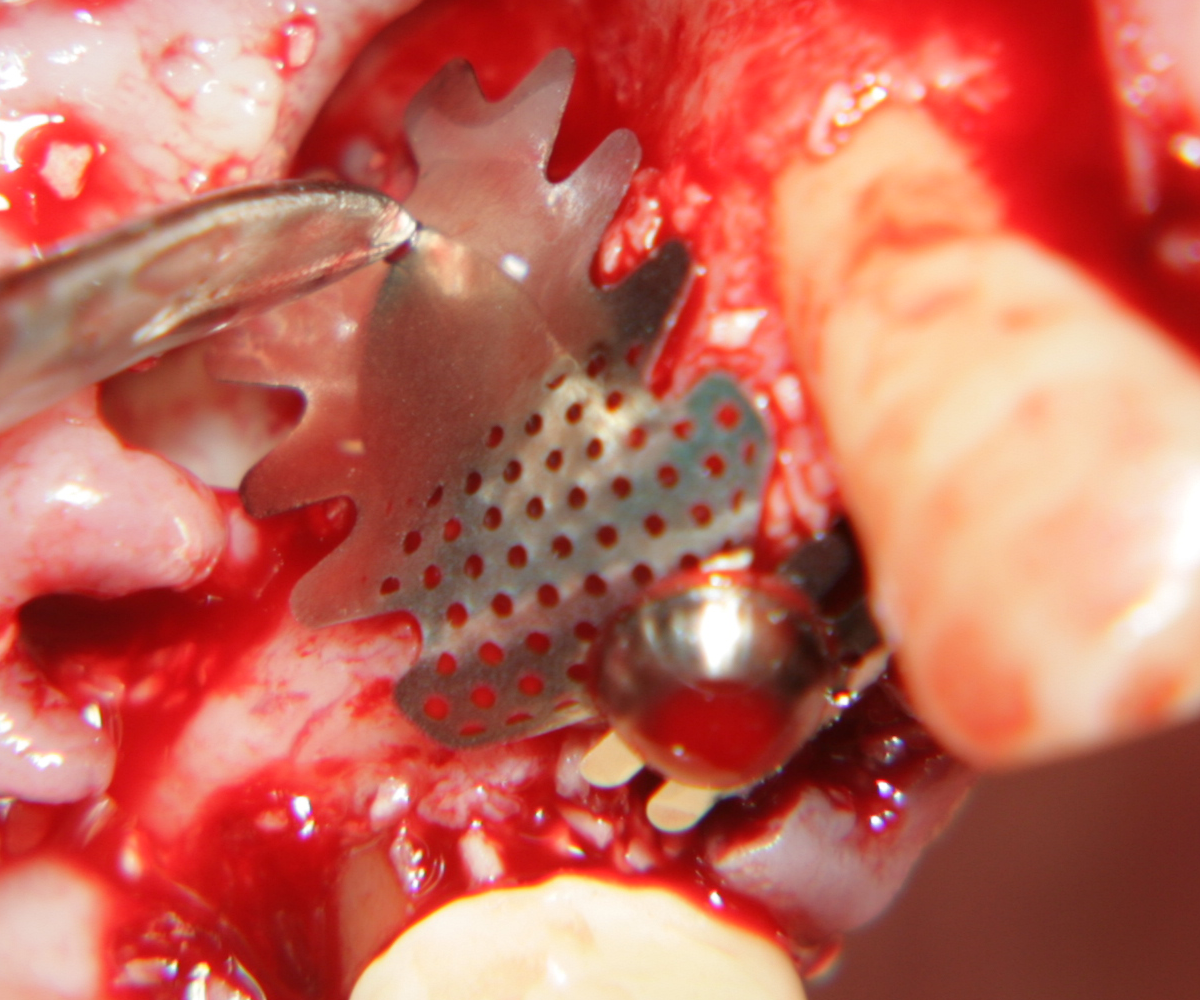

Титановите мембрани са твърди, ригидни приспособления, които се поставят в участъци с необходимост от увеличаване на костния обем - най-вече в областта на имплантологията, но също при радикуларни кисти и много рядко след екстракция на ретинирани мъдреци, при дефкетни фрактури, пострезекционни дефекти на челюстите, тежки остеомиелити и специфични възпаления на костта. Идеята на титановата мембрана е да предпази меките тъкани от колапс, поне за известен период от време, през който период под мембраната да започне костообразуване. През първите шест - осем месеца титановата мембрана оказва своя ефект, след което вече е безсмислено да остава в устата на пациента.

При операции с цел изграждане на допълнителн костна тъкан (костна пластика) винаги е добре да се перфорира кортикалната пластинка на костта. През тези перфорации излизат костни клетки, които постепенно прорастват в котозаместващия материал и синтезират нова костна тъкан. Перфорациите могат да се извършат с кръгло борче или с АСМ - фрезата на Neobiotech - Южна Корея.

Tent screw - винтове за

фиксиране на титановата мрежа

Около винтовете се поставя костозаместител, добре е да се размеси с

автогенна кост

Титанова мембрана

PRF